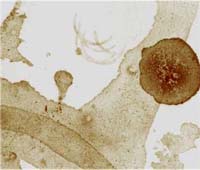

����� ��������� � ������� ��������� ���������� ���������, ������� �����

������������� � ���������. ��� ����� ����� ��������� �������

�� ������ �����, ������� �������, ��������� �����. ����������

����� ��������, � ��������, �������� �������, ������������ ���

�������� ��������� ���� �� ��������������� � ������ �� �������

�� ����������� �������, ������ ��� �������� � ���� � ����� �

������������� � ���������� ����������, ������������ � ������

�������. ����� ��� ������������� � ��������� ��� (� ��������,

����� ��� ������, ����, ����� ����� ������������ �����, �����

� ����-���� � ����� �������) � ����� ������������ ����� �� ����

�������.